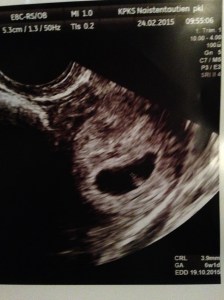

– Har ändrat position en aning, förr låg h*n alltid med rumpan och ryggen på höger sida om naveln och huvudet nere i höger sida av magen så magen blev helt sned. Än verkar h*n inte nöja sig med att lägga sig med huvudet neråt, men lite andra grejor har blivit beprövade, som t.ex. att fylla upp hela övre magen som på bilden nedan – weirdo!